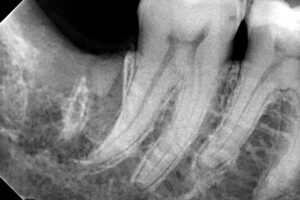

Εξαγωγή φρονιμίτη με έντονη κάμψη ρίζας

Ο ασθενής προσήλθε στο ιατρείο με σκοπό την εξαγωγή του κάτω δεξιού φρονιμίτη, ο οποίος τον πονάει πολύ τις τελευταίες μέρες. Η λύση θεραπείας ήταν η εξαγωγή του δοντιού, η οποία πραγματοποιήθηκε την ίδια μέρα μετά από τη χορήγηση κατάλληλης ποσότητας αναισθητικού. Την επόμενη μέρα ο ασθενής επέστρεψε φυσιολογικά στις καθημερινές υποχρέωσες του χωρίς να πρηστεί ή να πονά. Η εξαγωγή πραγματοποιήθηκε χωρίς καμία επιπλοκή όπως, σπάσιμο ρίζας κτλ.